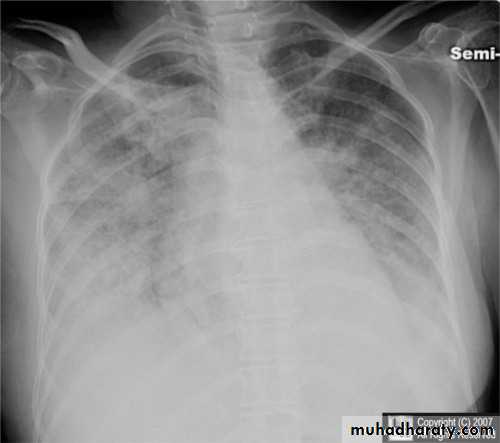

Pulmonary edema ( alveolar pulmonary edema)CXR of ault ,PA view shows:Bilateral patchy opacity mainly in the middle zones of the lungs (Bat wing sign )Cardiomegaly